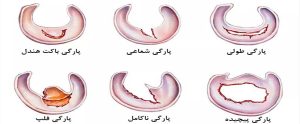

اشکال مختلفی از پارگیهای منیسک وجود دارد، بسته به شکل و محل آنها وقتی در اسکن انجام شده توسط دستگاه تصویربرداری (MRI) دیده میشود.

انواع مختلفی از اشکال پارگی مینیسک زانو وجود دارد که از مهم ترین آنها می توان به:

- پارگی دسته سطلی منیسک ( باکت هندل ) : نزدیک به ۱۰ درصد از پارگی های منیسک در این دسته قرار می گیرند. حرکت طبیعی زانو معمولا غیرممکن است زیرا قسمت پاره شده منیسک باعث قفل شدن زانو می شود.

- پارگی شعاعی منیسک : این یکی از رایج ترین انواع پارگی است. حدود ۲۸ درصد از تمام پارگی های منیسک داخلی در این دسته قرار می گیرند. این پارگیها هم بر روی استخوان درشت نی و هم بر محور بلند رشتههای منیسک عمود میشوند. این بدان معنی است که آنها می توانند با ایجاد اختلال در ساختاری که به توزیع وزن در زانو کمک می کند، فشار بیشتری را بر روی مفصل وارد کنند. این پارگی از لبه داخلی منیسک شروع می شود و تا کپسول ادامه می یابد و در قسمت میانی منیسک ایجاد می شود. پارگی شعاعی منیسک جانبی ، اغلب همراه با پارگی رباط صلیبی-قدامی دیده می شود. این نوع پارگی در قسمت بدون رگ منیسک رخ میدهد که خونرسانی خوبی ندارد؛ بنابراین توانایی بسیار کمی برای ترمیم خودش دارد. به همین علت پارگی شعاعی منیسک اغلب اوقات نیاز به مداخله پزشکی و جراحی دارد.

- پارگی فلپ منیسک: پارگی فلپ منیسک زانو، فرم دیگری از آسیب زانو است که شیوع کمتری دارد. اگر پارگی فلپ منجر به قفل شدن زانو شود، حتما نیاز به جراحی دارد. دو نوع پارگی فلپ وجود دارد، افقی و عمودی.هنگامی که شما دچار پارگی فلپ افقی هستید، سطح تحتانی و فوقانی منیسک ممکن است آسیبی نبیند، که در مورد پارگی فلپ عمودی صدق نمی کند.

- پارگی پیچیده منیسک : نوعی از پارگی منیسک زانو است که متاسفانه مجموعهای از چند نوع پارگی را شامل میشود. به دلیل ماهیت پیچیده این پارگی، منیسک توانایی کمی در ترمیم خود دارد و جراح در اغلب اوقات مجبور به خارج کردن قسمت آسیب دیده منیسک میشود.

- پارگی های درون منیسکی | پارگیهای ناکامل: پارگیهای درون منیسکی را بسیار فراوان میبینیم. اغلب این نوع پارگی، نشان از آغاز تغییرات دژنراتیو در منیسک زانو دارد.

- پارگی طولی/عمودی منیسک : این نوع پارگی می تواند در هر نقطه ای از منیسک باشد. اگر این پارگی گسترش یابد ممکن است منجر به پارگی دسته سطلی شود. همچنین برخلاف پارگی شعاعی، احتمال ترمیمِ آن، بسیار بیشتر است.